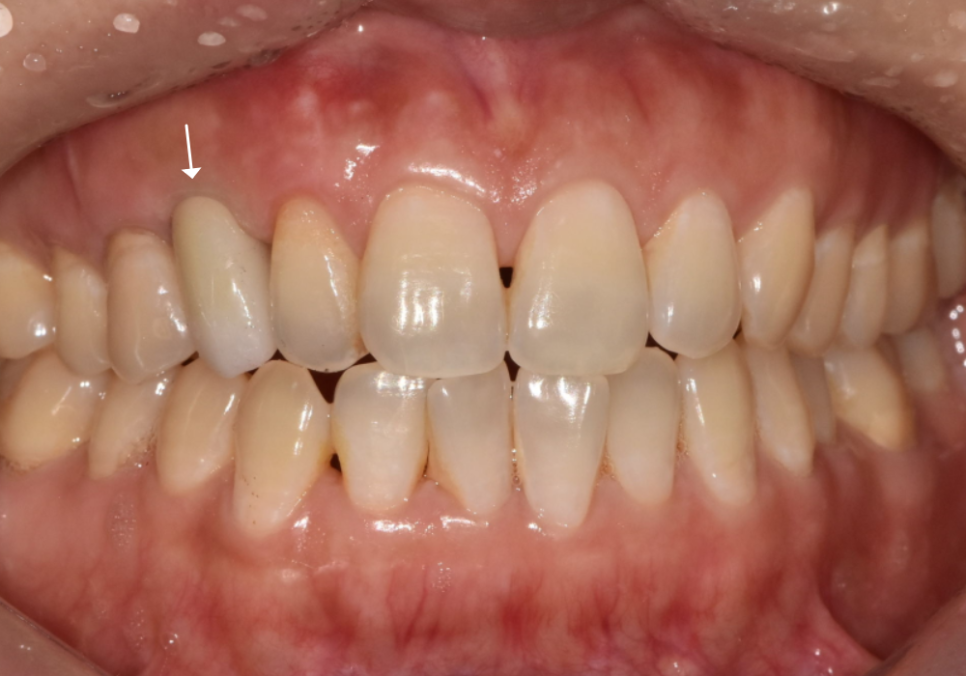

결과적으로 실제 가로폭은 좁지만,

260304

정면에서 보았을 때 ! 어떠세요?

그닥 작아보이지 않죠~

주변 치아와 자연스럽게 조화를 이뤄,

어색하지 않게 제작을 도와드렸습니다. ^^